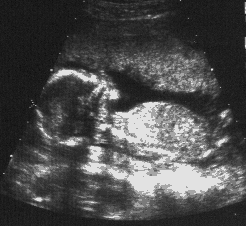

When I was very young, you could see my whole body in one

ultrasound screenful. By the time I got older, you could only see parts of my head or my face at one time. Other pictures of my head are this one and also this one.